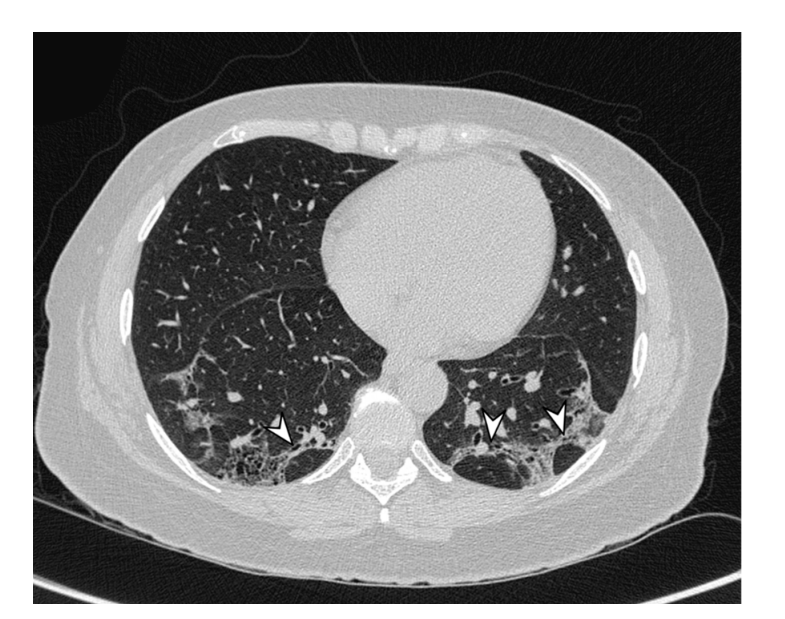

OP病变呈斑片状分布,病变中央是小气道;肺泡内、肺泡管见疏松的胶原样的结缔组织增生,形成Masson小体;肺泡内见肺泡巨噬细胞,部分肺泡巨噬细胞呈泡沫状,Ⅱ型肺泡上皮细胞化生。

图片

注:肺泡内的纤维灶称为Masson小体,光镜下表现为同心圆排列的纤维母细胞及肌纤维母细胞,呈息肉样。